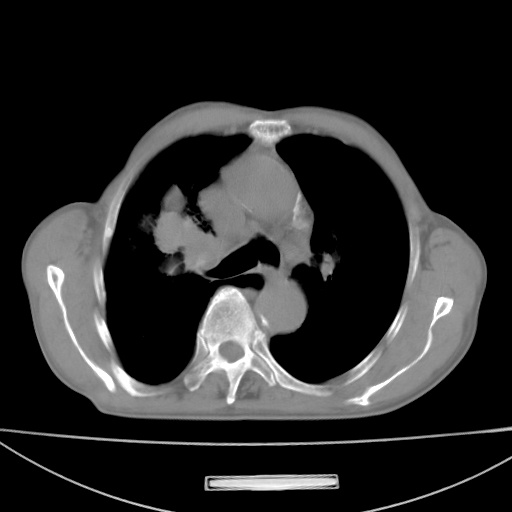

标题: CT13796:请会诊右上费病变!

患者男80岁,反复咳嗽多年,咳喘伴咯血1月

右上肺周围型肺癌伴肺门淋巴结转移.右上肺继发型肺结核.

右上肺周围型肺癌伴肺门淋巴结转移

右肺上叶占位性病变,考虑周围型肺癌,肺门淋巴结转移。要是能提供更多的临床资料就好了,以供鉴别诊断。

右肺尖周围型肺癌伴肺门淋巴结肿大

右肺上叶占位性病变,考虑周围型肺癌,肺门淋巴结转移。

右上肺周围型肺癌伴肺门、纵膈淋巴结转移

考虑为:右肺上叶肺癌伴阻塞性肺炎、右肺门及纵膈淋巴结转移。